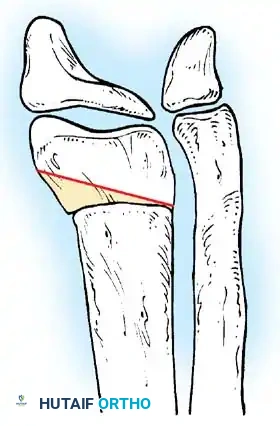

When conservative measures fail, surgical intervention is required:

1. Comprehensive Posteromedial Release (PMR): Involves lengthening of the Achilles, posterior tibialis, FDL, and FHL, along with extensive capsulotomies of the ankle, subtalar, and talonavicular joints.